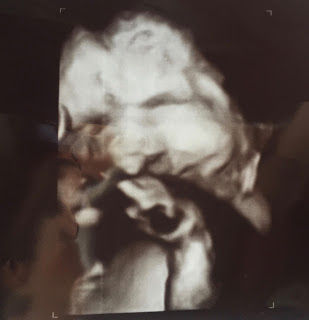

They are still concerned about other major issues, but at this point much we will wait until birth to find out what we are facing. Because of his position (he's breech) the ultrasound tech was having a difficult time getting clear shots. She was trying to show us more of his cleft issue, but it's hard to see in the ultrasound. I'm praying that we have a perfectly healthy baby who happens to have a cleft lip/palate. Or even more, praying that he could be healed completely. Want to see his little picture?

Our sweet baby. He is so loved!